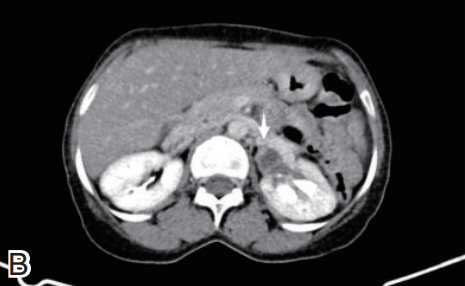

优化后确诊典型病例分享

基础信息:患者女,48岁,尿血吸虫虫卵阳性,偶左下腹隐痛,血清抗体1∶256,尿常规红细胞(+);采用定制CT方案(肾上极至膀胱下缘,100 kV/80 mA,术前40分钟服800 ml水充盈膀胱)。

影像表现与诊断价值:CT平扫示膀胱前壁增厚(图2A),左肾盂轻度扩张(1.8 cm,图2B),肾盏增宽,薄层重建及功能评估识别可逆性肾损伤。左输尿管下段管壁增厚(3 mm)、节段性狭窄(1.5 cm长,最窄1.5 mm),近端轻度扩张(图2C),延迟期清晰显示病变、减少肠道干扰。

干预与预后:吡喹酮治疗,1个月后复查示输尿管狭窄减轻、肾盂积水消失,肾功能恢复,精准诊断避免不可逆损伤。

图2

A:3 mm层厚泌尿系CT平扫轴位示膀胱前壁增厚约6 mm(箭头);

B:左肾盂轻度扩张(1.8 cm)(箭头),肾盏增宽;

C:左输尿管下段管壁增厚(3 mm)(箭头)、节段性狭窄(1.5 cm长,最窄1.5 mm)